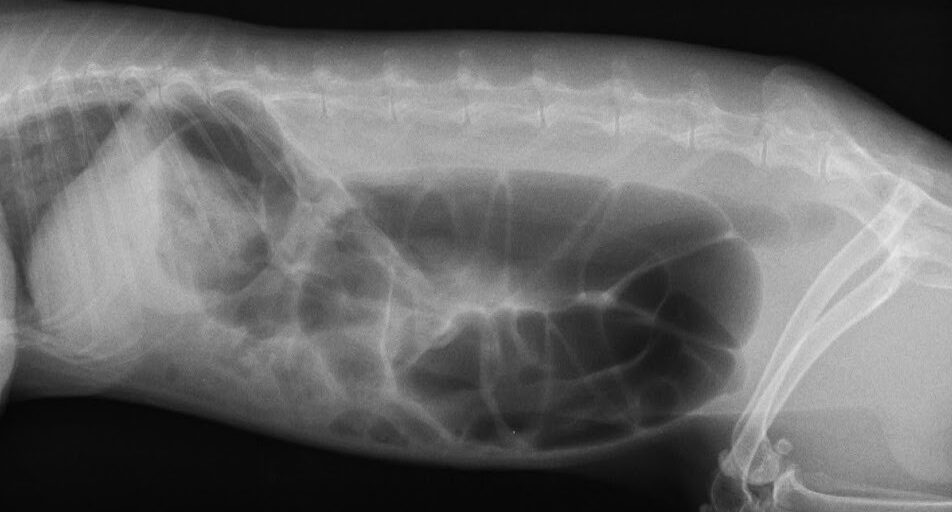

レントゲン検査 胃の大きさや内容物の状態、小腸・盲腸のガスの溜まり具合を確認します。鬱滞を引き起こす別の病気がないかどうかも確認します。

レントゲン写真① レントゲン写真②